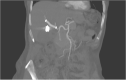

Presentation of case: A 76-year old female underwent laparoscopic cholecystectomy because of a severe acute on chronic cholecystitis. A massive arterial bleeding occurred during surgery, which was controlled with hemoclips. Approximately one week after surgery the patient developed severe colic pains and cholestatic liver enzyme alterations. Endo-ultrasound showed normal-width bile ducts, however during a subsequent ERCP haemobilia was observed. On computed tomography a pseudoaneurysm of the right hepatic artery was seen. Selective embolization was initially successful, however, a rebleed was observed two weeks later and a 6 × 50 mm Viabahn stent graft was placed in the right hepatic artery uneventfully. The patient remained free of complaints during 3-years of follow-up.